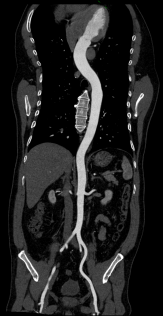

Chẩn đoán hình ảnh mô mềm tiên tiến cho vùng bụng.

Tăng cường độ tương phản I-ốt.

Hỗ trợ đánh giá an toàn cho bệnh nhân.

Đảm bảo hình ảnh chất lượng cao.